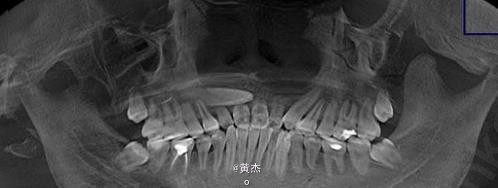

男,刘××,16岁。主诉:11、21牙齿疼痛一周。病史:一周前患者自觉前牙疼痛难忍,未做任何处理。遂来我院牙体牙髓科治疗。牙体牙髓科检查:11、12松动Ⅱº,21松动Ⅰ°。11、21叩诊+++。

在11、21根管内放置牙胶尖后做x光检查:11、21牙根吸收至根中2/3.。 21未吸收,但测不到长度。正畸科通过CBCT检查,建议拔除13.。姑息保留11、12及手术探查21的根尖情况。

诊断:11、21根尖周炎。处理:11、21开髓无活力,大量血性渗出,根管无法测量。于是转诊口腔外科。术前和患者签知情同意书。给患者讲明外科手术有可能失败,最终拔除11、12、21的可能性。口腔外科处理:拔除13.。发现 11牙根几乎完全吸收、21唇侧牙根也被13牙冠压迫吸收到根中1/3。于是术中行11、21MTA根尖区封闭。12暂不做处理,观察半年后考虑进一步治疗方案。